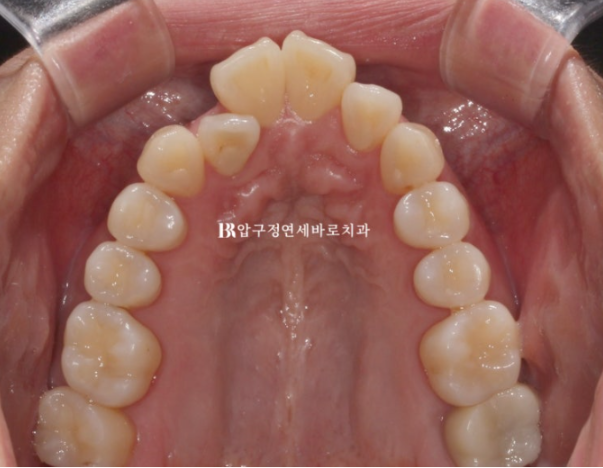

입천장에 위치하는 측절치

24.02

위에는 안보이는 설측 2D장치를 아랫니는 작은어금니 덧니까지 배열하기 위해 MTA 장치를 추천드렸습니다.

위에는 설측 장치를 붙였고 중간 스튜디오 촬영도 문제 없을 것 입니다.

24.07 2D 설측 장치 교정

설측장치인 2D 부분교정용 장치 모습입니다.

뒤로 붙이니 교정기간 내내 보이지 않습니다.